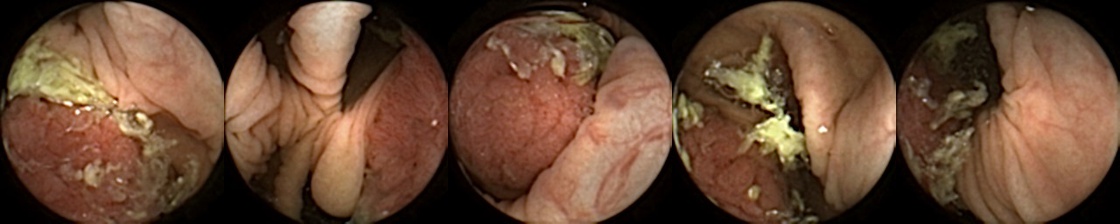

Figure 3 shows classification output examples for the MIV model using the pretrained ConvNext. Note that the model has a test accuracy of 83.66% for DBA L2 with 2 heads. In each row, the leftmost image is the query and the four images to the right of each query are the target images. The True Positive (left-top) and True Negative (bottom-right) examples outline the cases when the model is able to successfully distinguishes images containing unique polyps from those with dissimilar polyps. The False Negative (top-right) and False Positive (bottom-left) examples show the cases where the model fails to correctly distinguish images of unique polyps and images of dissimilar polyps. Further, we can note from the differences in the examples of True Positives and False Negatives that when the query image and the target set instances differ from each other in some ways, then the model can misclassify images. These differences could be attributed to different views due to the dynamics of the camera inside the colon, different views from two camera heads of the capsule, or presence of artifacts such as bubbles, debris, and small bowel secretions.

On the other hand, when we look at the examples of False Positives (Pred = true, Label = false) in Figure 3, we can note that if images in the target match the query in ways such as texture, color, illumination conditions, presence of artifacts, then this may lead to misidentification of the query as belonging to the targets. For True Negative (Pred = false, Label = false) examples, we can see that presence of significant differences between the query and the targets leads to correct identification of the image sets as different.

True Positive False Negative

False Positive True Negative

Figure 3: True Positives (Pred = true, Label = true), False Negatives (Pred = false, Label = true), False Positives (Pred = true, Label = false), True Negatives (Pred = false, Label = false) for the DBA L2(h=2) model using the pretrained ConvNeXt. In each row, the leftmost image is the query and the 4 images to the right of each query are the target images.